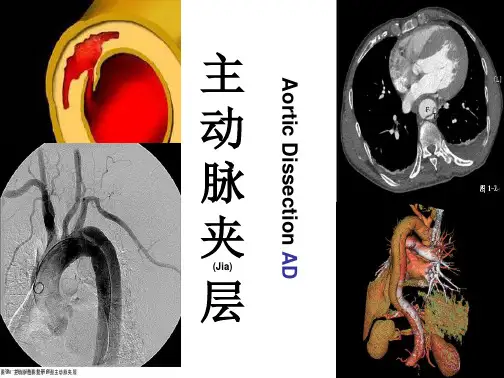

主 动 脉 夹

(Jia)

层

Aortic Dissection AD

解剖(Po)结构

正常的人体动脉血管由内膜、中膜和外膜3层结构 组成。而动脉夹层是(Shi)指由于内膜局部撕裂,受到 强有力的血液冲击,内膜逐步剥离、扩展,在动脉内

形成真、假两腔。